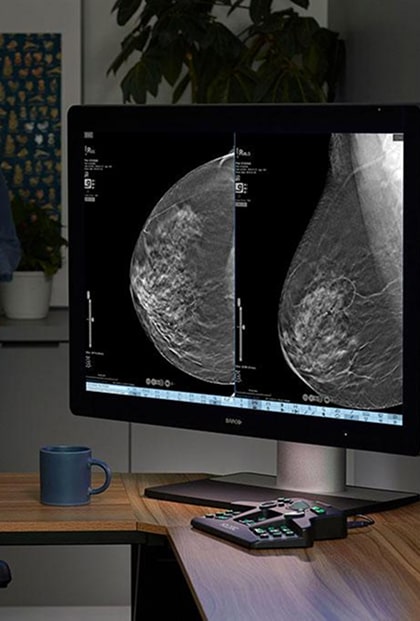

SecurView Reading Workstation

The Hologic SecurView reading workstation has been a trusted solution for years, delivering high-quality imaging and advanced diagnostic tools. With 80 years of collective experience and the largest inventory of refurbished Hologic equipment, MedSource Imaging offers expertly refurbished SecurView workstations, ensuring reliable performance and high-quality standards at a cost-effective price.